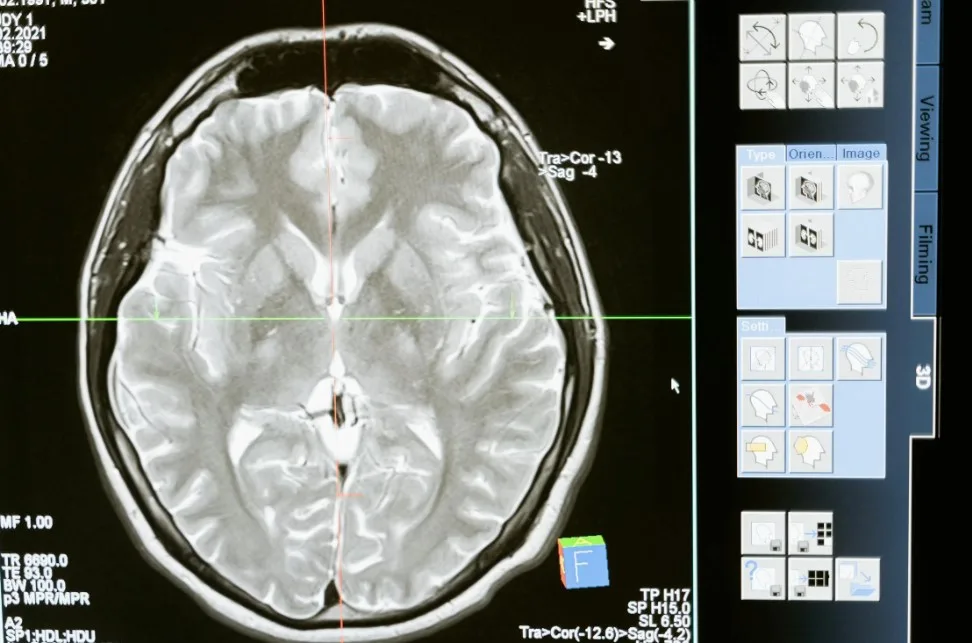

Барселона, Испания. Исследователи, финансируемые ЕС, изучают, могут ли нанотехнологии однажды стать более безопасной и менее инвазивной альтернативой медикаментозному и хирургическому лечению серьезных заболеваний головного мозга.

Санчес-Вивес возглавляет трехлетнюю исследовательскую инициативу “МЕТА-МОЗГ”, финансируемую ЕС, которая продлится до декабря 2026 года. Команда изучает новые способы взаимодействия с мозгом, сочетая нанотехнологии, ультразвук и усовершенствованный мониторинг мозга.

Команда META-BRAIN, в которую входят ученые и клиницисты из ведущих исследовательских институтов Европы, включая Австрию, Кипр, Италию, Испанию и Швейцарию, разрабатывает беспроводные, минимально инвазивные методы восстановления мозговой активности.

Команда META-BRAIN изучает минимально инвазивные способы дистанционного и точного управления нейронной активностью, стремясь взаимодействовать с нейронами без постоянных имплантатов или открытых операций на головном мозге.